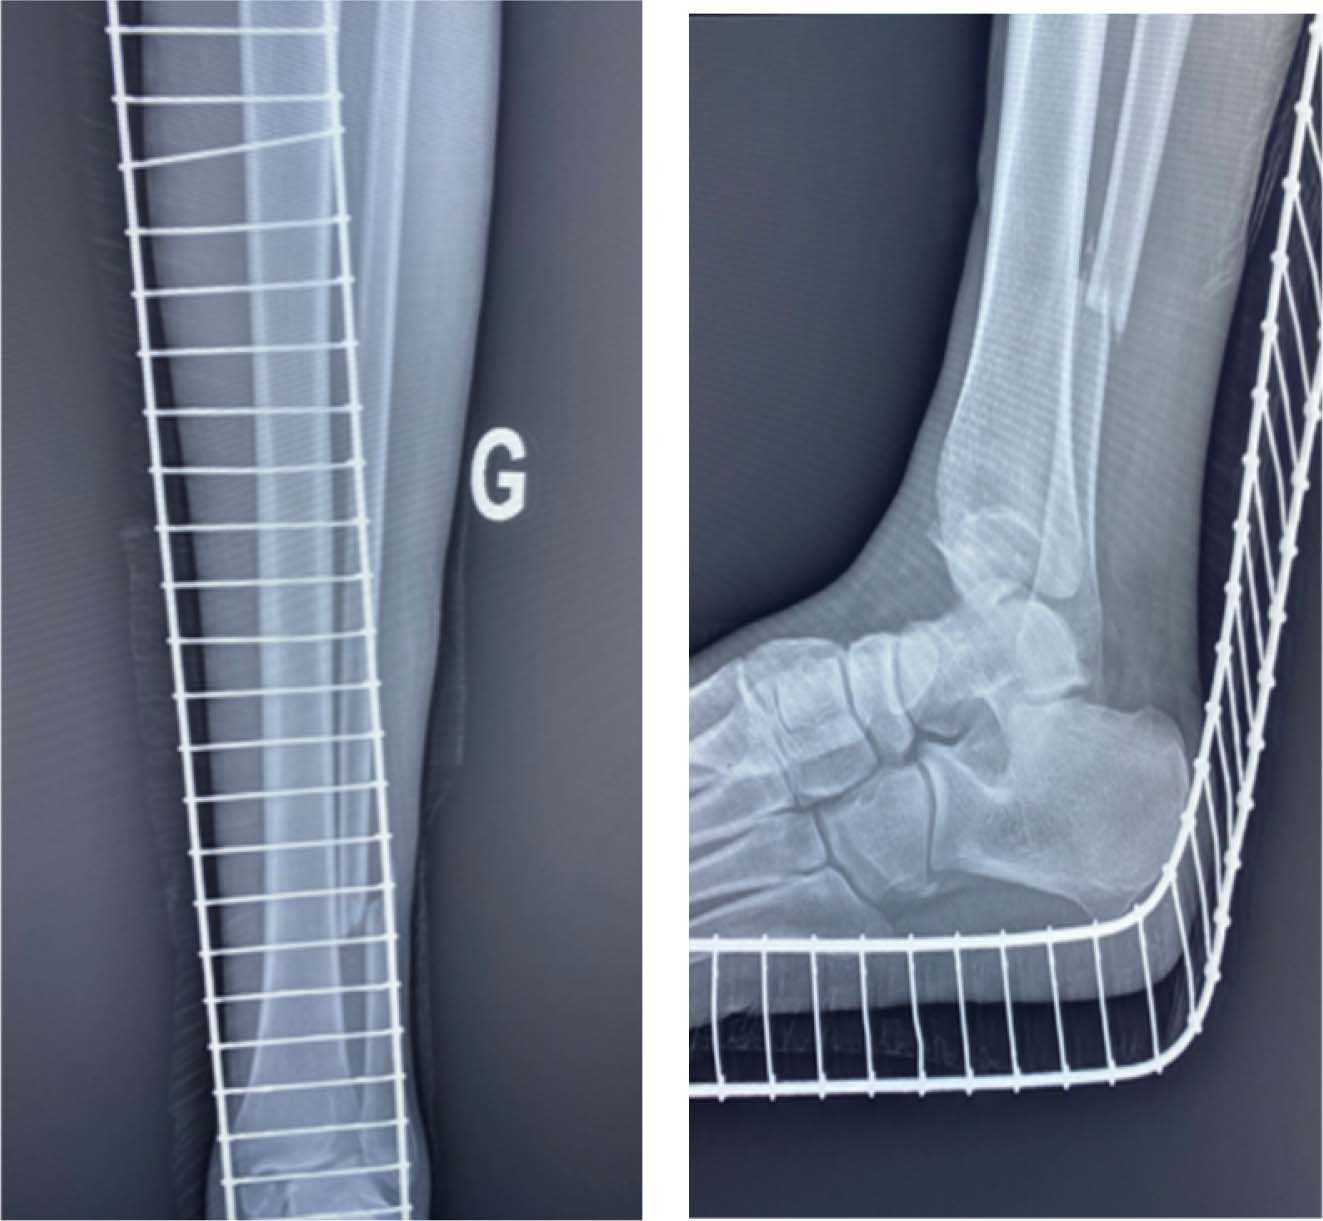

A 32-year-old male patient suffered from a bimalleolar fracture of the ...

Ankle Fractures - The bimalleolar ankle fracture with syndesmotic ...

MANAGEMENT OF BIMALLEOUS FRACTURE .pptx